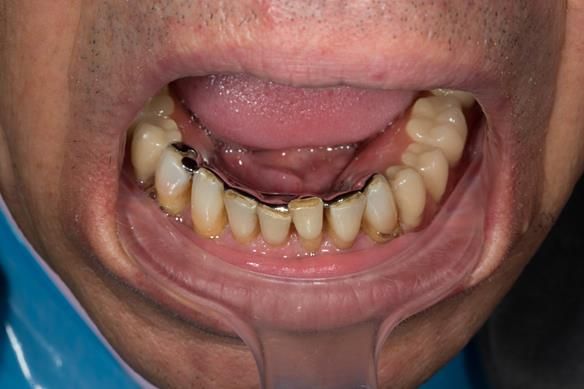

- Extraction of all upper teeth and LR5 and LL4 and fitting of immediate acrylic based (Mk 1) dentures - complete upper and lower partial

- Definitive dentures (Mk 2) – complete upper metal reinforced and lower cobalt chromium based partial of hygienic Scandinavian design to be made 9 - 12 months after extractions of all upper teeth and LR5 and LL4

The clinical situation and treatment process is shown in detail below with photographs.

The patient has been successfully rehabilitated and is now having periodontal maintenance from Syed Abad, Specialist in Periodontics at the practice. His quality of life has improved considerably. The clinical prosthodontics was provided by me and the technical work by Rowan.